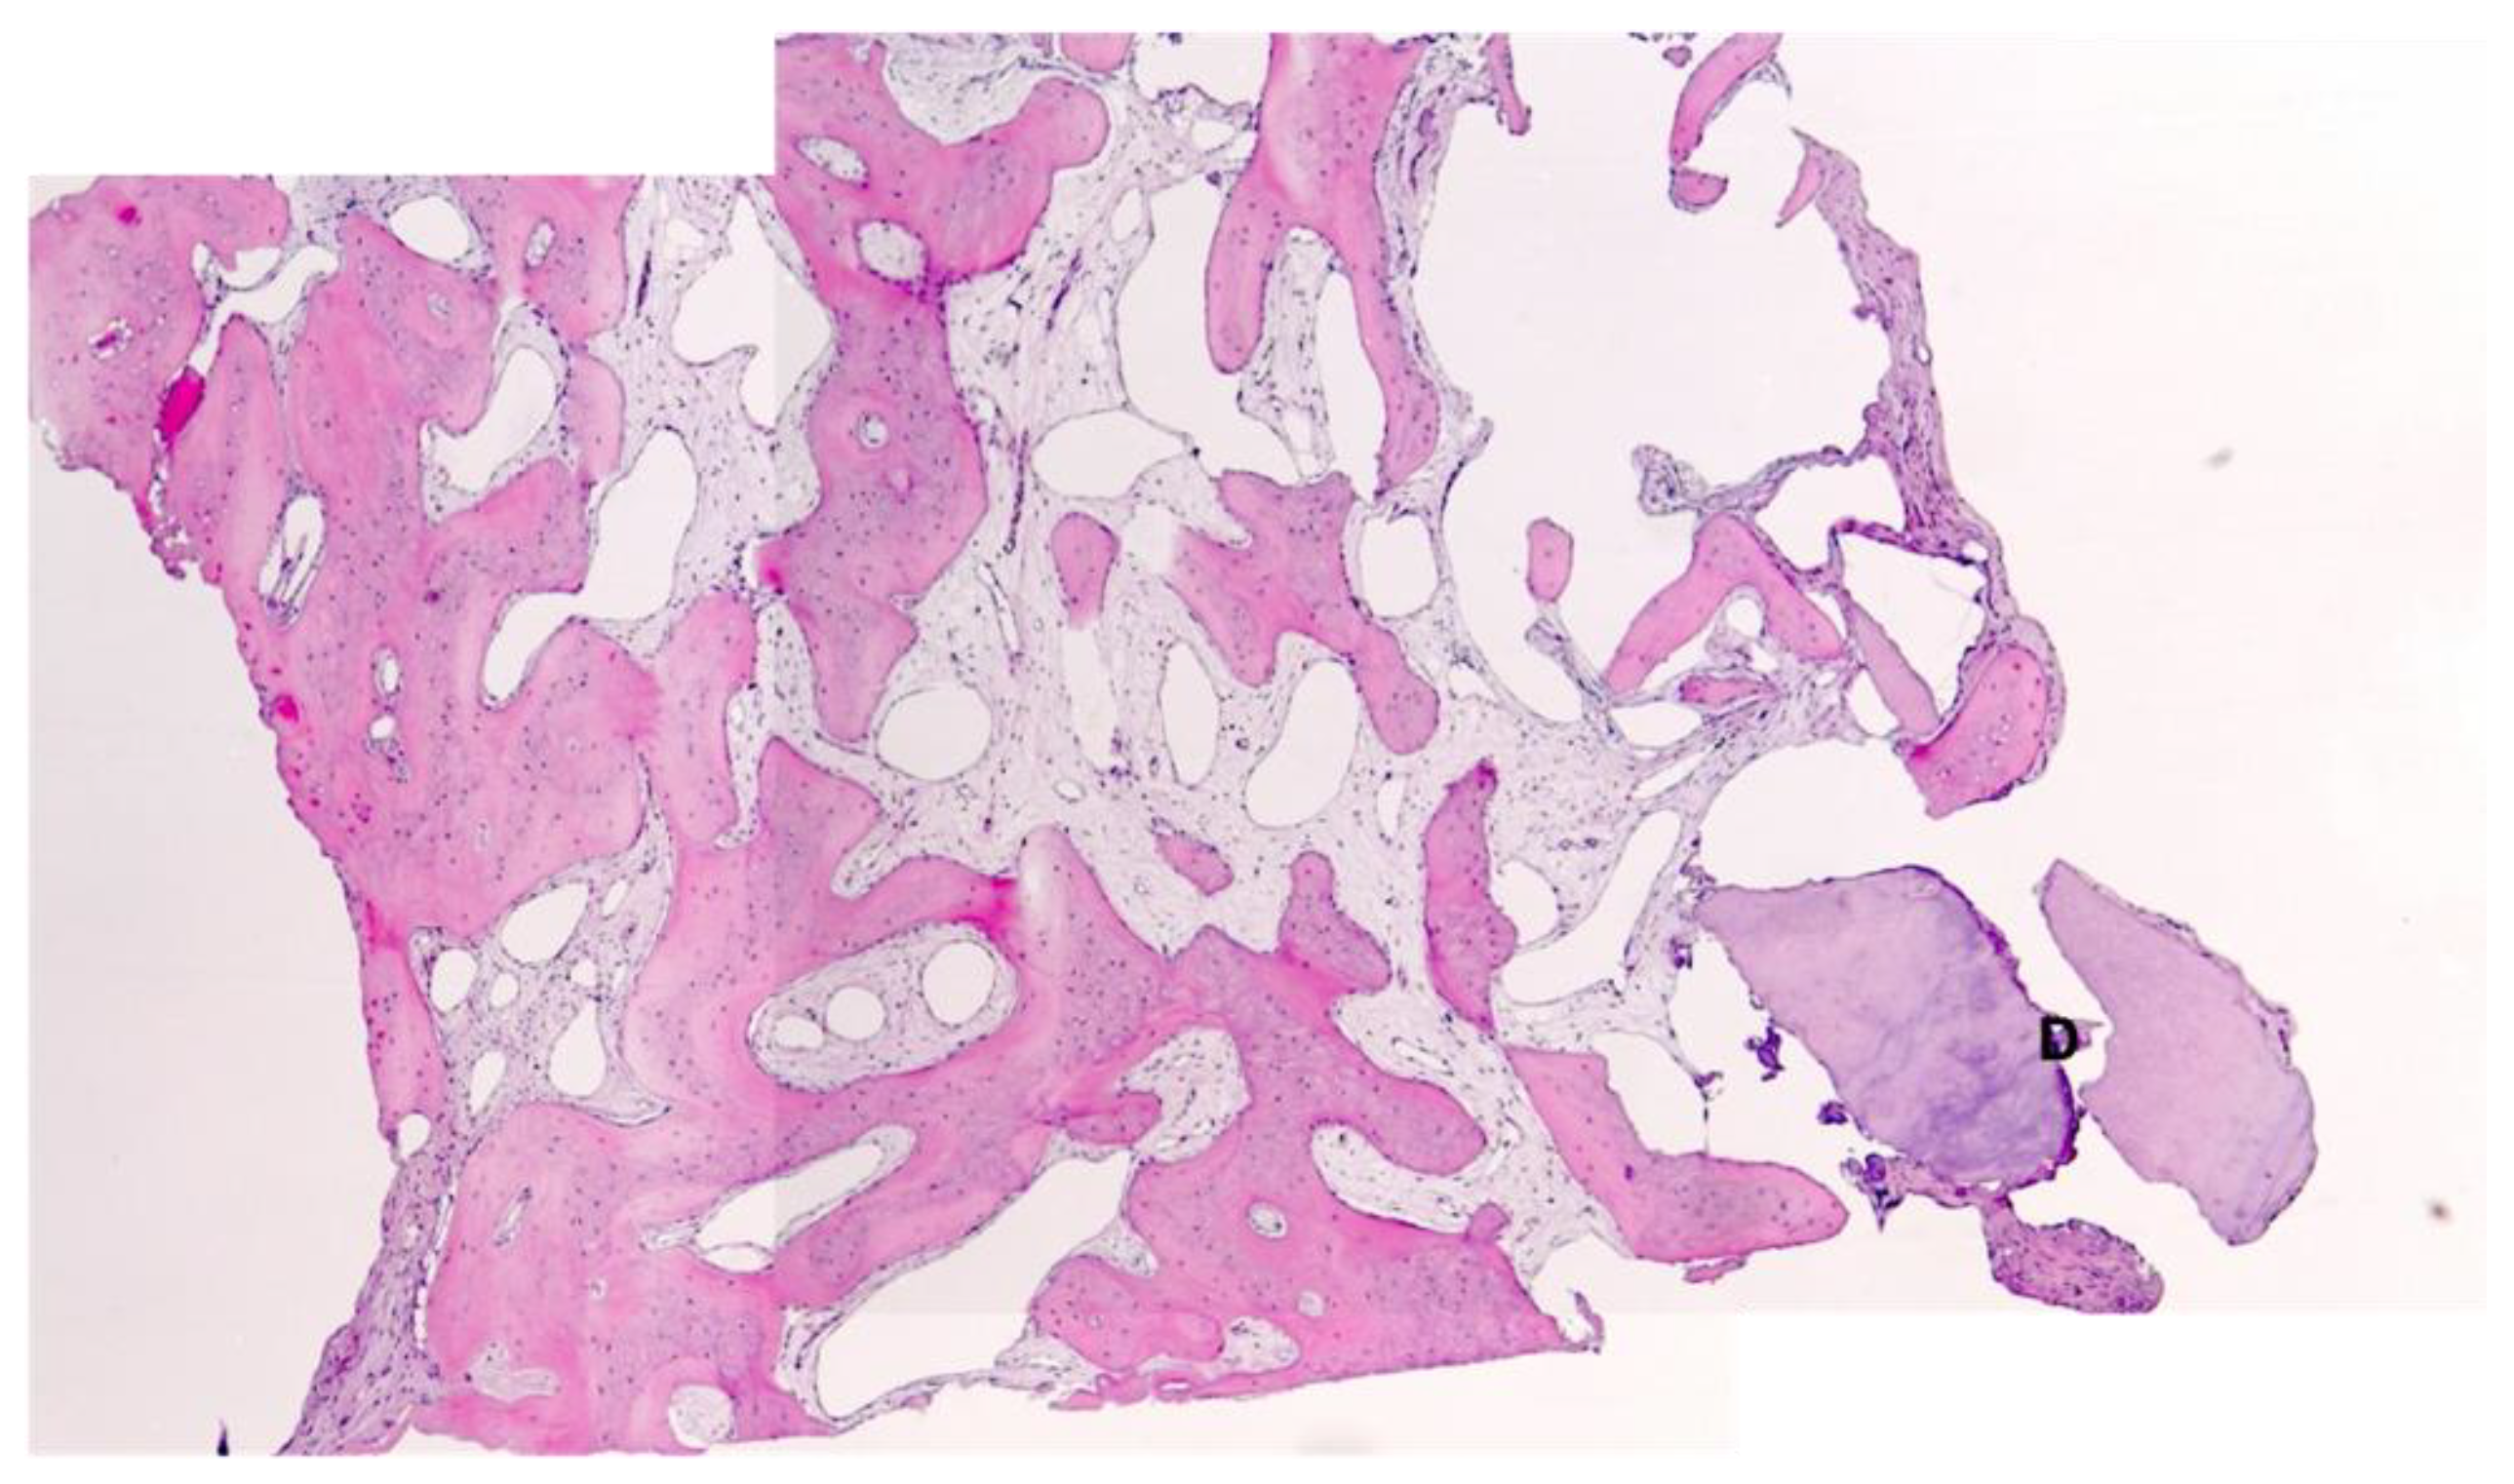

Histological Analysis

3.1. Bone Quality